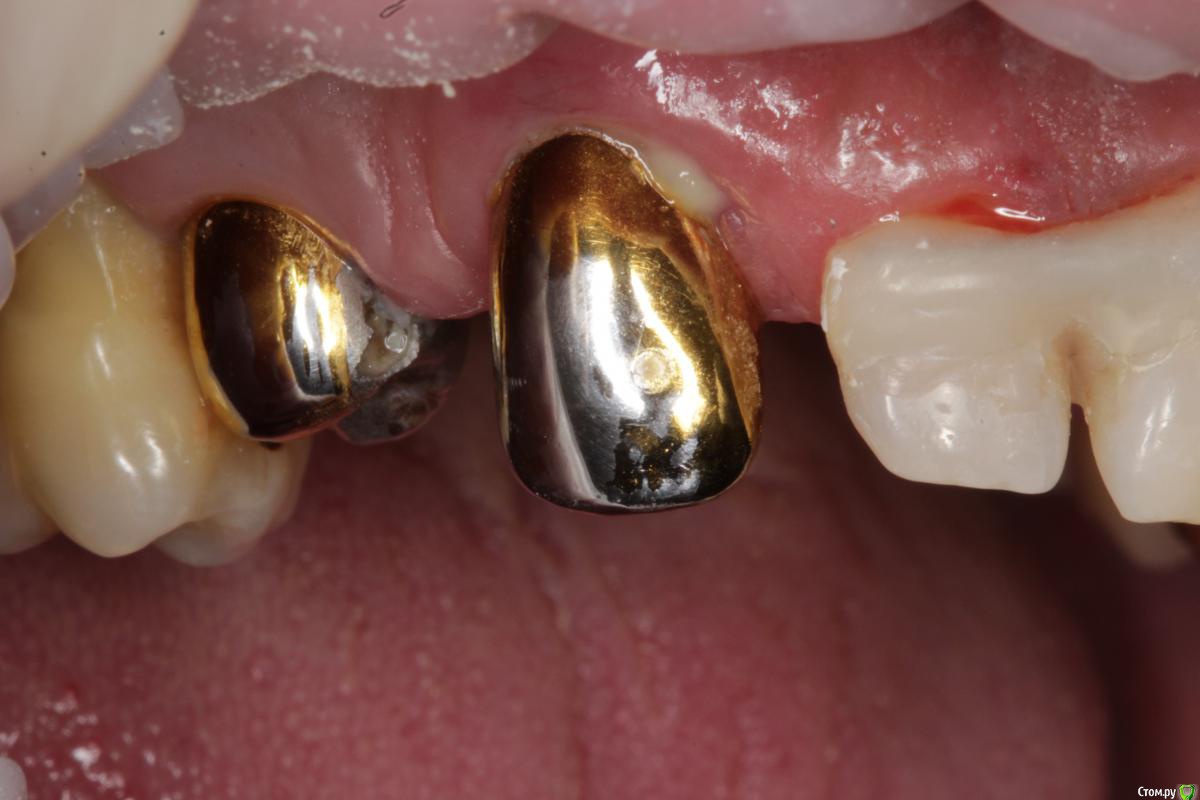

Витторио Орлионе Опубликовано 4 июля, 2018 Поделиться Опубликовано 4 июля, 2018 очень прошу мудрого совета у вас дорогие коллеги!!! Пациента беспокоят выделения из под десны, при осмотре выявлен карман глубиной 5 мм, зуб витален и стратегически нужен для дальнейшего лечения, потому что пациент хотел бы реабилитировать верхнюю челюсть, причиной всего этого как мне кажется стал нависающий край коронки, можно ли добиться стабилизации процесса сняв коронку проведя глубокий скейлинг, чтобы в будущем взять этот зубик под опору в мостовидном протезе или лучше на него все таки не расчитывать и удалить... Ссылка на комментарий

Dr.Mikitos Опубликовано 4 июля, 2018 Поделиться Опубликовано 4 июля, 2018 очень прошу мудрого совета у вас дорогие коллеги!!! Пациента беспокоят выделения из под десны, при осмотре выявлен карман глубиной 5 мм, зуб витален и стратегически нужен для дальнейшего лечения, потому что пациент хотел бы реабилитировать верхнюю челюсть, причиной всего этого как мне кажется стал нависающий край коронки, можно ли добиться стабилизации процесса сняв коронку проведя глубокий скейлинг, чтобы в будущем взять этот зубик под опору в мостовидном протезе или лучше на него все таки не расчитывать и удалить...Зуб подвижный? если нет, то глубокий скейлинг, закрытый кюретаж, наблюдение. Если все хорошо, заполировать уступ, покрыть коронкой. Если же зуб подвижный, то вся та же схема, только по мере необходимости можете добавить открытый кюретаж. Но по фото, все должно быть хорошо! Ссылка на комментарий

krokomot Опубликовано 5 июля, 2018 Поделиться Опубликовано 5 июля, 2018 НИкакой закрыты скейлин и кюретаж не поможет, это мертвому припарка, если хотите улучшить состояние, нужно раскрывать корень, скейлинг, рут планинг и полишинг, обработка корня, лоскут натянуть, но тут нужен опыт определенный. 2 Ссылка на комментарий